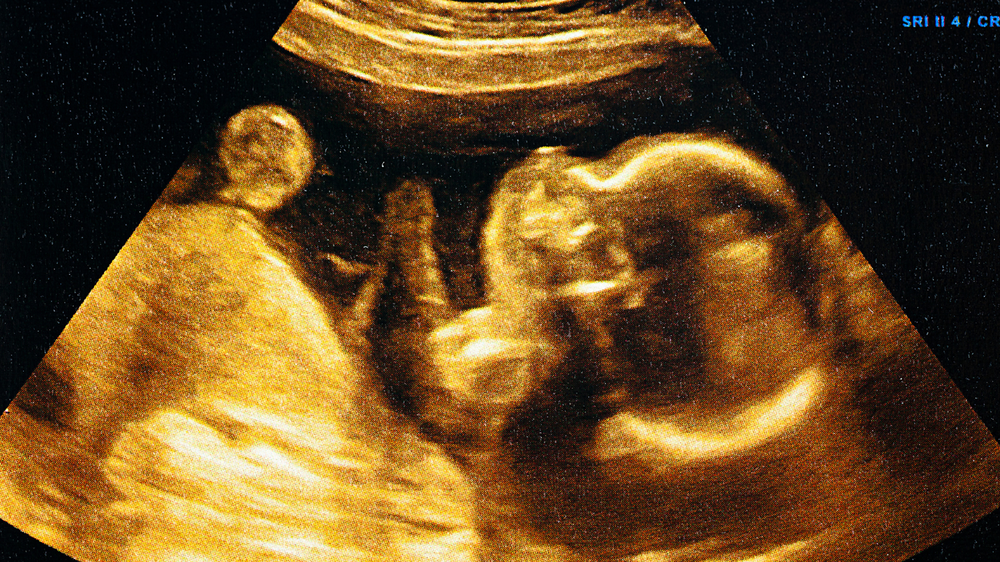

The development of your baby inside the womb progresses with your pregnancy journey, including the development of small features like eyelashes and eyebrows. These may appear to be small things, but they serve a purpose; they contribute to protecting your baby’s eyes after birth. Knowing how and when such significant formations take place can give you clarity on how well your baby is growing and help you feel more in tune with the changes taking place during your pregnancy.

When you enter the second trimester of your pregnancy journey, typically between the 12th and 16th week, the formation of your baby's eyebrows and eyelashes starts taking place. At this point, hair follicles start to develop in the areas above the eyes and along the eyelids.

Around week 20, these follicles become more active, and fine hair strands start to show up. These hairs are very soft and light, but that’s a key step in the formation of your baby’s face.

3. Can sonography scans show eyebrows and eyelashes?

In most routine scans, these fine details aren't clearly visible. Their development is usually confirmed after birth.